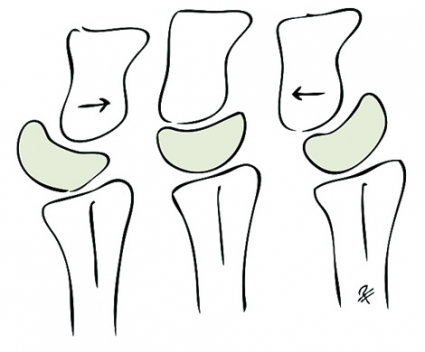

Skafolunära ligamentskador. När det gäller skafolunära ligamentskador är ligamentet mellan scaphoideum, trapezium och trapezoideum (STT), volara ligamentet mellan scaphoideum och capitatum (SC) och volara ligamentet mellan radius, scaphoideum och capitatum (RSC) viktiga s k sekundära stabilisatorer. När dessa ligament gradvis tänjs ut resulterar det i en karpal kollaps med statisk instabilitet som följd. På en röntgenbild i obelastat läge framträder då en volar flexionsfelställning av scaphoideum och en dorsal rotation av lunatum (DISI). Vanligtvis finner man då på röntgenbilden också ett »ring sign« i scaphoideum till följd av scaphoideums rotation.

Lunotrikvetrala ligamentskador leder också med tiden till karpal kollaps. I sent skede ses då VISI-felställning (volart roterad lunatum) och sekundär artros. Den lunotrikvetrala instabiliteten är inte alltid klart symtomgivande men däremot ofta associerad med andra skador, t ex i triangulära fibrokartilaginära komplexet (TFCC).